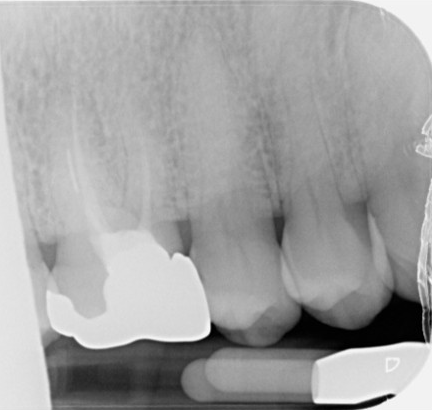

Pre-operative

Post-operative